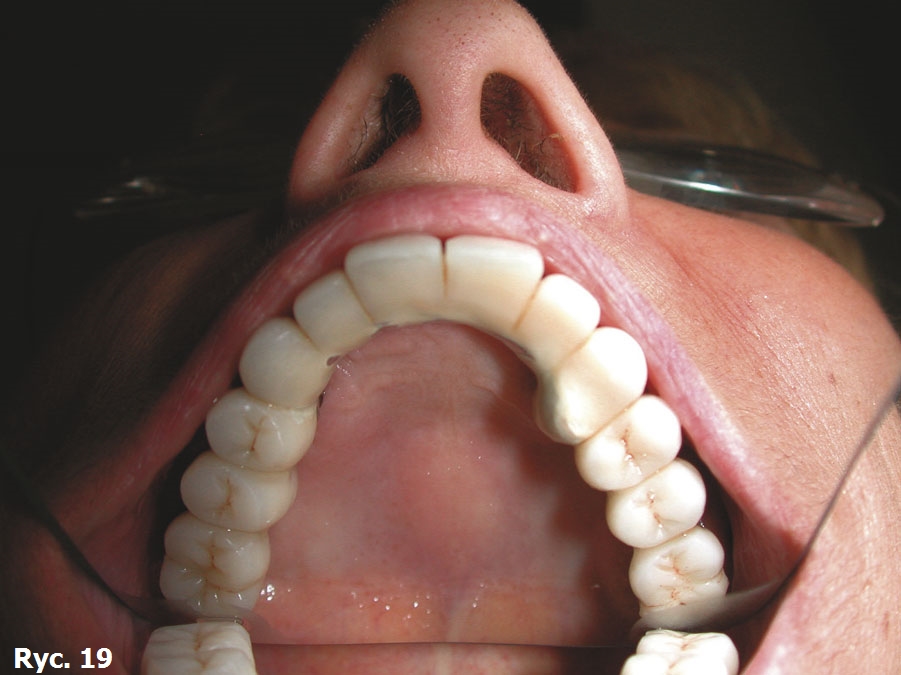

Obrazy TK oraz modele stereolitograficzne ukazują wysoki stopień zaniku tkanek twardych szczęki. Z tego powodu wykonano projekt wszczepu podokostnowego full arch (ryc. 14), który odlano z 5. gatunku tytanu (ryc. 15) i wszczepiono. Zabieg odbył się bez powikłań (ryc. 16). Leczenie zakończyło się wykonaniem i oddaniem protezy stałej full arch typu all on four, która w pełni zaspokaja estetyczne oraz funcjonalne oczekiwania pacjentki (ryc. 17, 18, 19, 20, 21).